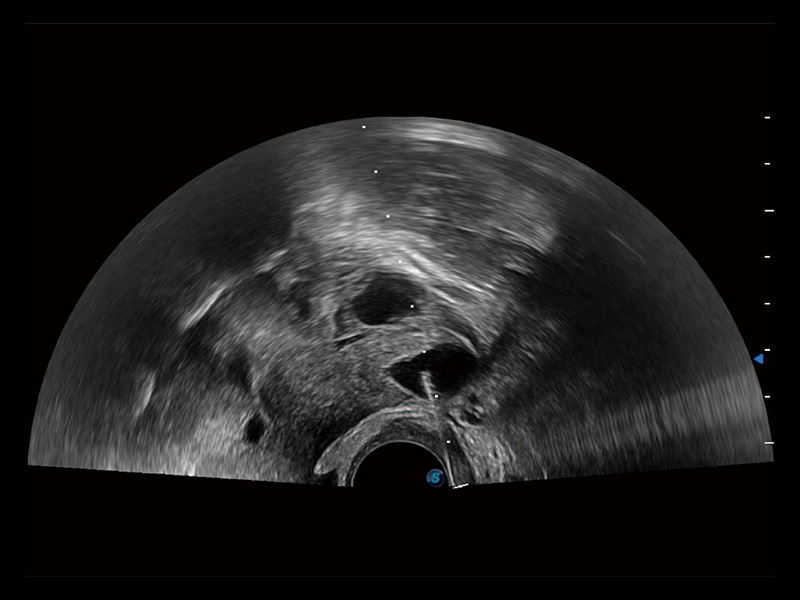

卵巢多囊样改变

宫外孕血流